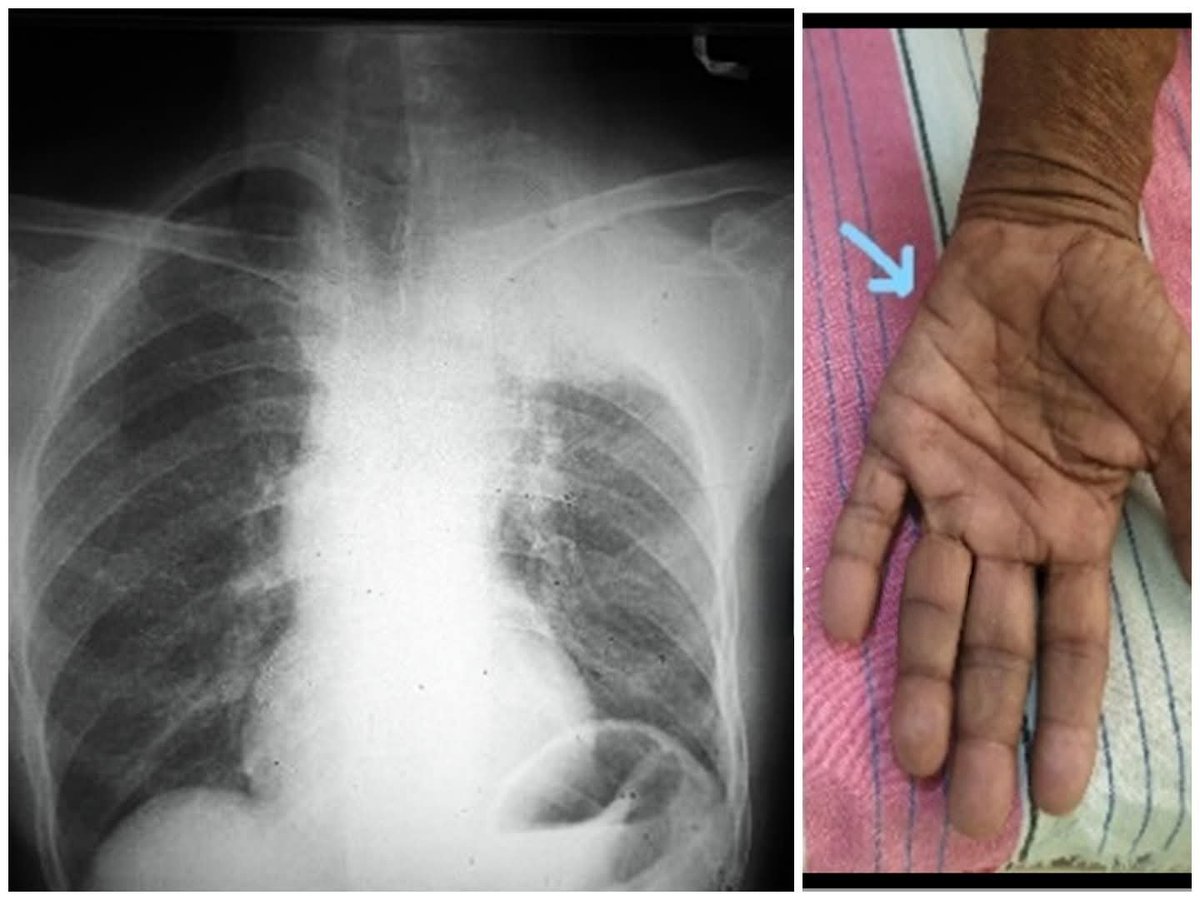

A 60-year-old man presented with a cough and left-sided numbness and weakness in his hand. What are the findings? What is the diagnosis? #medical #MedTwitter #FOAMed @DrAkhilX @IhabFathiSulima @Dr_Shiv_kumar_ @Ausbones @hemo_shk